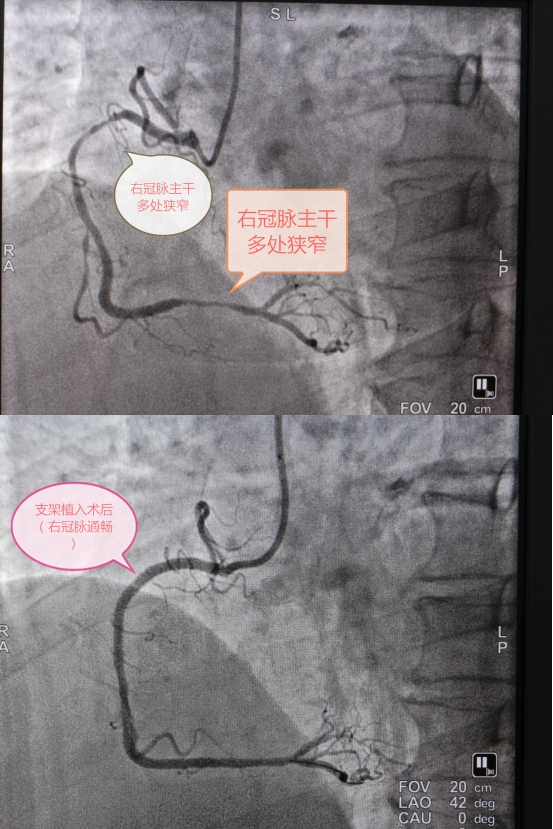

图片1.jpg

图上:右冠脉主干多处狭窄;图下:支架植入术后(右冠脉通畅)

图上:右冠主干完全闭塞;图下:支架植入术后(右冠脉主干通畅)

当病人已经发生心梗,能否最快时间开通梗阻的血管,是挽救生命健康的关键。马军在医生的安排下,在该院介入中心做进一步检查,经冠脉造影检查很快便找到了病变部位:冠心病RCA闭塞性病变。

该院特聘国药东风总医院心血管学科带头人闵新文教授与该院急危重症医学科主任严文军、心内科主任周三军根据屏幕上的造影结果进行现场分析,显示血管完全闭塞,这种情况需继续进行介入治疗,经充分与患者及家属进行沟通同意后,决定为他植入支架,方能保持冠状动脉管腔的开放,降低心梗再次发生率。

手术台上,专家们身披重达十余斤铅制围脖、铅衣,准备工作完毕后开始进行介入治疗,经过一个小时,两枚支架成功植入了冠脉,造影显示RCA病变消失,术后,患者立感胸闷减轻,仿佛获得了“重生”。